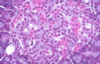

Alpha and beta cells in islet of Langerhans

Allows differentiation bw alpha and beta cells in islet of Langerhans. Beta cells stain more purple, alpha cells stain more pink. Most cells are beta cells, especially the ones in the middle

Beta cells in pancreas

Stains the insulin that is secreted by beta cells, beta cells stain darker